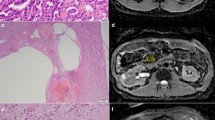

Through linear regression, images taken at various b-values can then be used to calculate the apparent diffusion coefficient (ADC) in a particular region of interest. With respect to focal renal lesions, solid malignancies typically display lower ADC values than benign lesions, possibly related to the high cellular density of tumors with intact cell membranes that impedes the Brownian motion of water molecules. One meta-analysis of 17 studies has demonstrated that ADC values can help distinguish between benign and malignant RCC tumors with RCC tumors displaying significantly lower ADC values than benign kidney tissue [8].

Although ADC values of RCC tumors have been well-analyzed by previous studies, no study has yet examined the b-values of DW-MRI with respect to RCC. This is of clinical importance, as factors aside from passive diffusion, such as capillary perfusion, can contribute to decreased signal-to-noise ratio (SNR) in low b-value DW-MRI [10]. On account of this signal decay, low b-value DW-MRI becomes less qualitative and more quantitative, since it must be based on complex ADC calculations. Therefore, as low b-value DW-MRI does not facilitate qualitative detection of malignancies which may adversely affect diagnostic accuracy, the objective of this study was to determine the comparative diagnostic performance of standard b-value (800–1000 s/mm2) versus low b-value (400–500 s/mm2) DW-MRI in the detection of RCC.

RCC tumors are unique due to the presence of hemosiderin deposits, a phenomenon which has proven useful in their differentiation from other tumor types [32, 33]. According to a recent study by Childs et al., the paramagnetic effect of hemosiderin is likely responsible for in-phase signal intensity losses and T2*-induced intravoxel dephasing commonly observed in RCC lesions [32]. This local magnetic susceptibility-induced intravoxel dephasing is important to DW-MRI of RCC lesions since a greater degree of intravoxel dephasing results in greater loss of signal intensity [31]. This phenomenon may contribute to the limited sensitivity of DW-MRI for the diagnosis of malignant renal masses observed here (i.e., 0.59 for standard b-value DW-MRI and 0.58 for low b-value DW-MRI). Raising the b-value increases the degree of diffusion weighting (i.e., increases the signal loss caused by the diffusion of water molecules along the direction of the applied gradient), which increases the contrast between tissues with different diffusion coefficients while also decreasing the overall signal intensity and SNR [34]. Thus, the underlying loss of signal intensity from hemosiderin-induced intravoxel dephasing combined with the loss of signal intensity from applying a higher b-value may explain why standard b-value DW-MRI displayed an overall inferior diagnostic accuracy over low b-value DW-MRI in detecting RCC lesions here (AUC of 0.62 for standard b-value DW-MRI vs. 0.68 for low b-value DW-MRI).